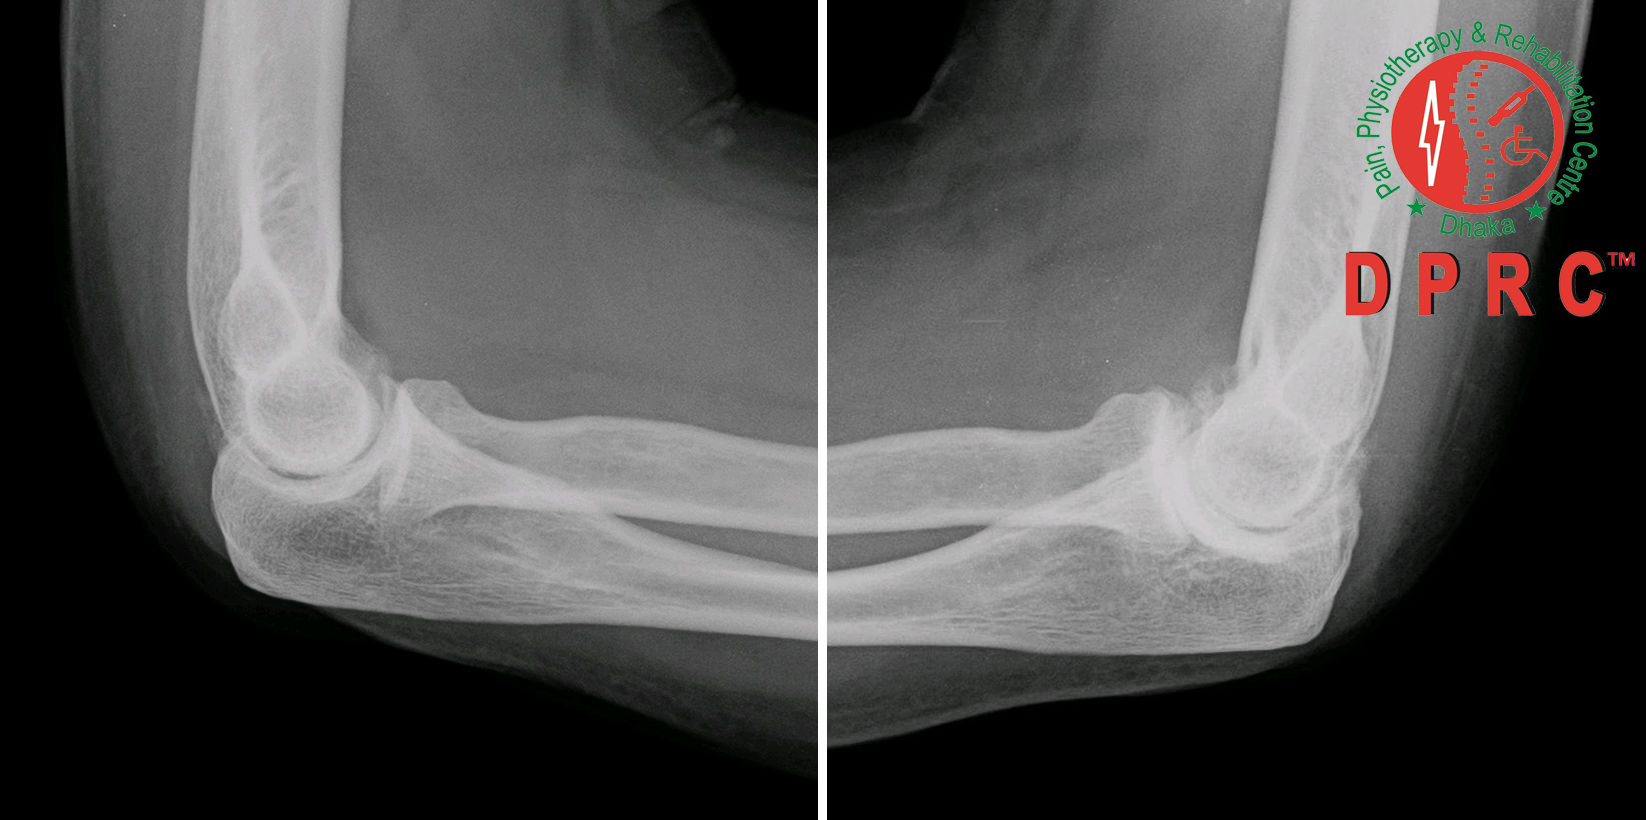

বিভিন্ন ধরনের আর্থ্রাইটিসের মধ্যে সবচেয়ে কমন হচ্ছে- অস্টিওআর্থ্রাইটিস। অন্যনাম ডিজেনারেটিভ আর্থ্রাইটিস। শরীরের বিভিন্ন জয়েন্টে হাড়ের শেষ প্রান্তে যে কার্টিলেজ থাকে তা একটা কুশনের মতো কাজ করে। ক্রমাগত মুভমেন্টের ফলে জয়েন্টর হাড়ের মধ্যে ঘর্ষণ হয়। এই ঘর্ষণের কারণে সম্ভাব্য ক্ষয়ের হাত থেকে রক্ষা করে কার্টিলেজ। নানা কারণে এই ক্ষয় হতে হতে এই কার্টিলেজের টোটাল ক্ষতি হয়। এর ফলে অস্টিওআর্থ্রাইটিস হয়, জয়েন্টে ব্যথা হয় ও মাবিলিটি কমতে থাকে। জয়েন্ট মার্জিনে নতুন হাড় তৈরী হয়। অস্টিওআর্থ্রাইটিস স্পাইনে হলে বলা হয় স্পন্ডাইলোসিস। যেমন: গাঢ়ে হলে সারভাইকেল স্পন্ডাইলোসিস বা কোমরে হলে লাম্বার স্পন্ডাইলোসিস।

হাঁটু, কোমর, হাত ও পায়ের আঙ্গুল, স্পাইন, কনুই, রিস্ট, এংকেল প্রভৃতি স্থানে সচরাচর অস্টিও আর্থ্রাটিস হয়।